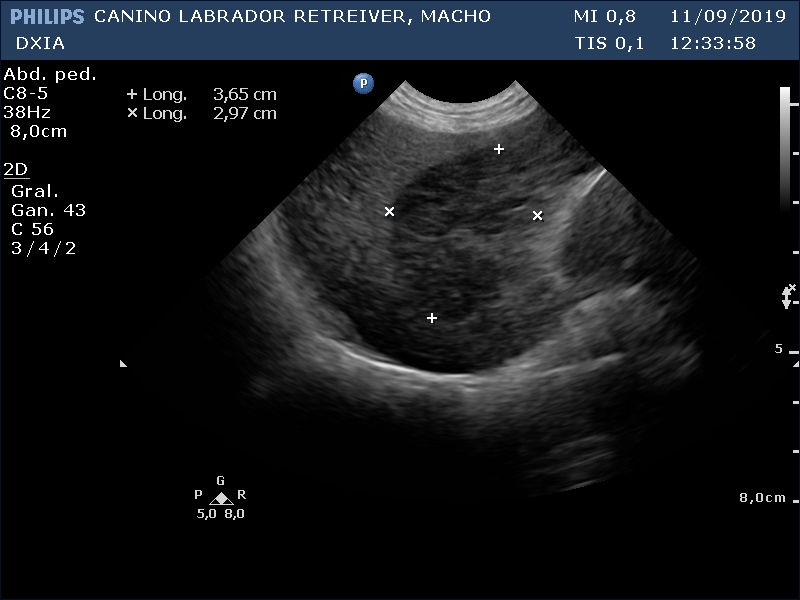

Primera Imagen Hígado DXIA Scott

Primera Imagen Hígado donde se obtuvo la PAF